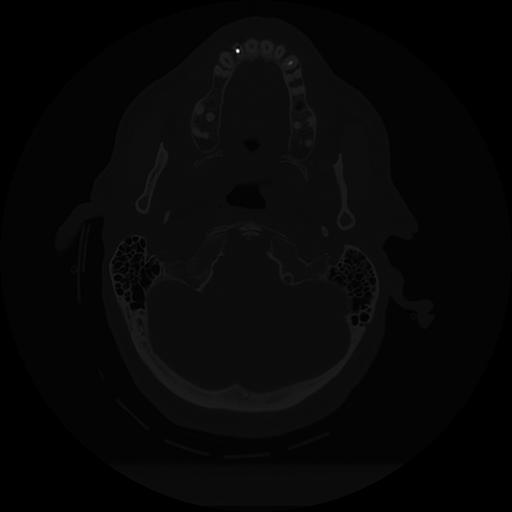

11 HUESO,,Axial,2.0,HUESO,,